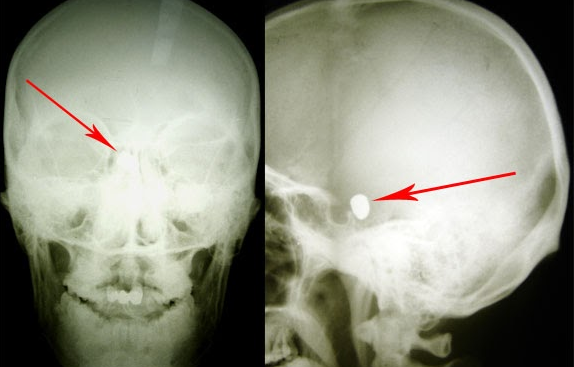

Tânărul a fost împușcat în regiunea temporo-parietală stânga, glontele rămânând intracerebral. Din spusele mamei, s-a întâmplat în Germania, unde tânărul își făcea studiile. Acesta s-a aflat în comă aproximativ trei luni jumate. Când și-a revenit prezenta afazie mixtă și lipsa vederii la ambii ochi. S-a tratat în România, iar la Chișinău pacientul a fost internat pentru investigații și tratament după ce în Germania și România a primit refuz de a fi operat din cauza gravității stării lui, pe motiv de prezența unui corp străin endocranian manifstat clinic prin retard mental, ataxie, ambliopie profundă bilaterală, pronunța doar unele silabe, dereglări de comportament, toate în evoluție stabilă, cu alterarea capacității de lucru și calității vieții pacientului.

„A fost foarte greu de localizat glontele. Nu exista încă neuronavigația. Am efectuat operația prin radiografia intraoperatorie. Cu greu am găsit glontele căci era amplasat în creier la o adâncime foarte mare. Succesul meu ca neurochirurg a fost nu doar extragerea glontelui dar și fapul că pacientul după operație putea sta în picioare, putea sta așezat, a început să perceapă unele comenzi de la cei apropiați iar când l-am externat mi-a dat mâna și și-a luat rămas bun. Bucuria mea a fost că tânărul a venit la Chișinău fiind adus pe targă dar a plecat stând așezat în mașină,” a mărturisit directorul INN, Grigore Zapuhlîh.

Starea după înlăturarea glontelui endocranian prin abord supraorbital stânga era satisfăcătoare, în ameliorare cu prezența mișcărilor spontane în toate extremitățile. Glontele a fost extras cu success fără apariția conplicațiilor neurologice. În două săptămâni pacientul fiind externat.